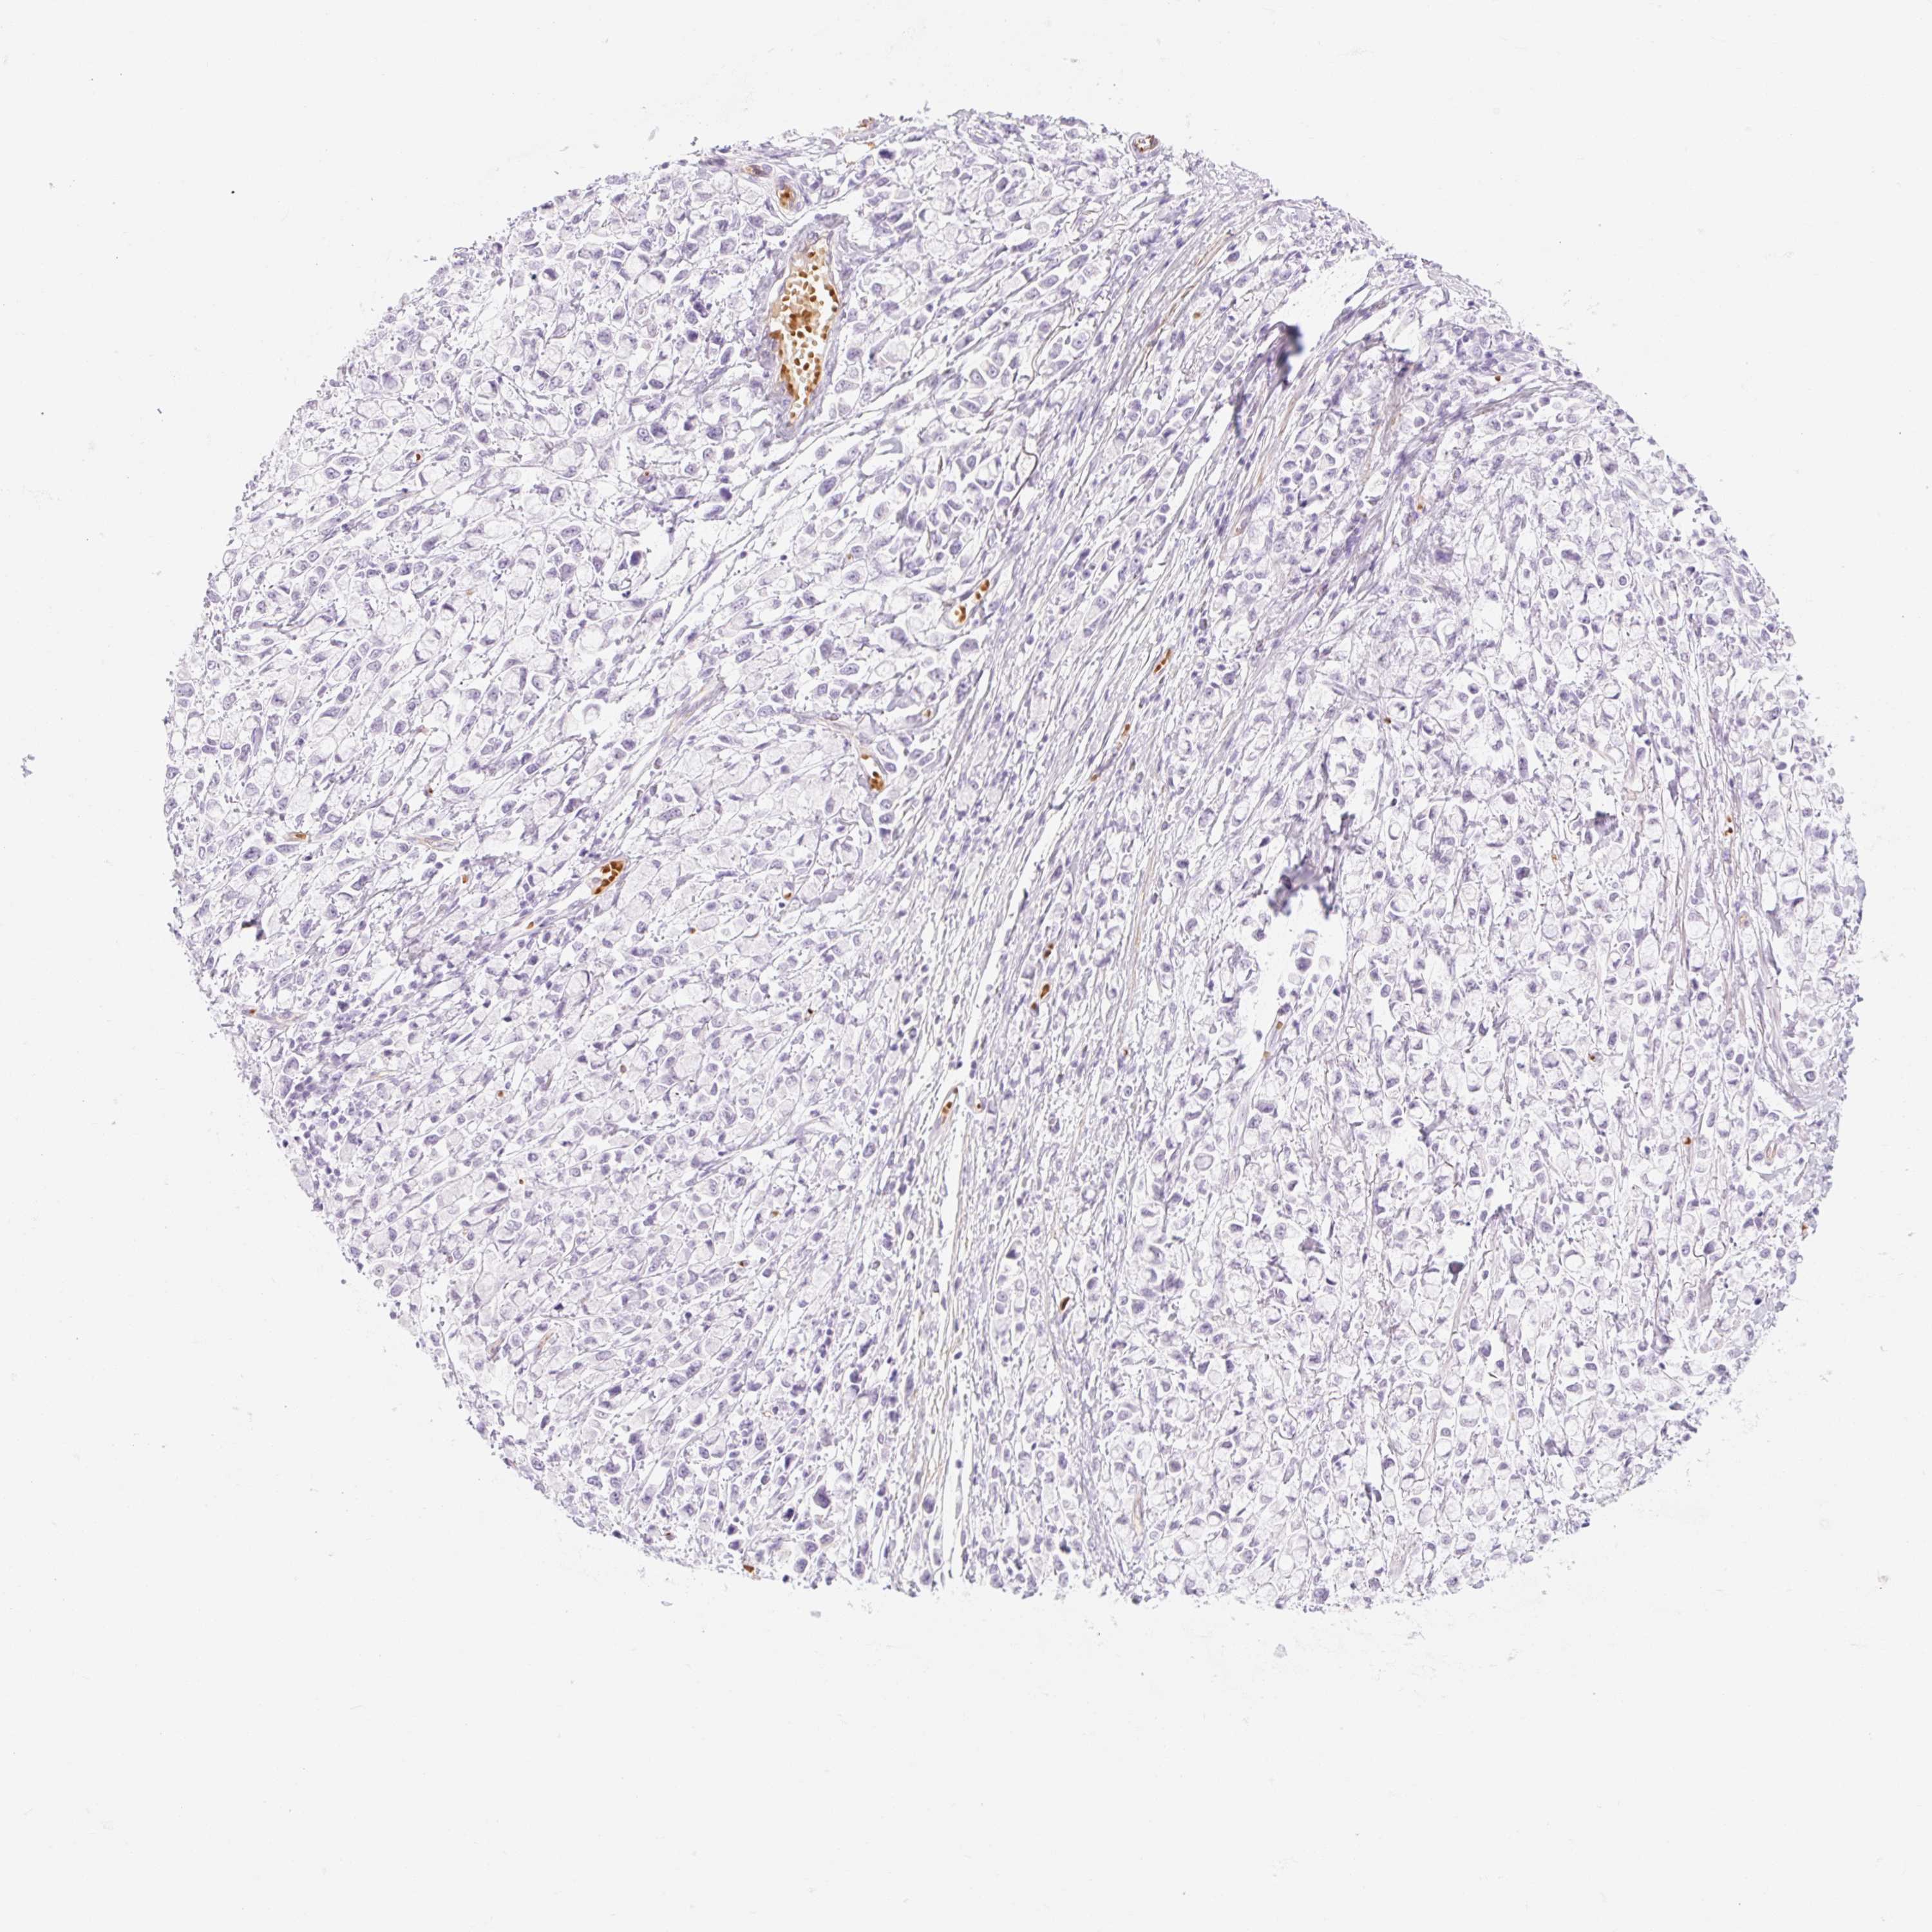

STOMACH CANCER - Protein expressioni

A mouse-over function shows sample information and annotation data. Click on an image to view it in a full screen mode. Samples can be filtered based on level of antibody staining by selecting one or several of the following categories: high, medium, low and not detected. The assay and annotation is described here.

Antibody stainingi

Antibody staining in the annotated cell types in the current human tissue is reported as not detected, low, medium, or high, based on conventional immunohistochemistry profiling in selected tissues. This score is based on the combination of the staining intensity and fraction of stained cells.

Each image is clickable and will lead to virtual microscopy that enables deeper exploration of all samples and also displays staining intensity scores, fraction scores and subcellular localization as well as patient and tissue information for each sample.

Antibody HPA056605

Staining

High

Medium

Low

Not detected

Intensity

Strong

Moderate

Weak

Negative

Quantity

>75%

75%-25%

<25%

None

Location

Nuclear

Cytoplasmic/membranous

Cytoplasmic/membranous,nuclear

Adenocarcinoma, NOS